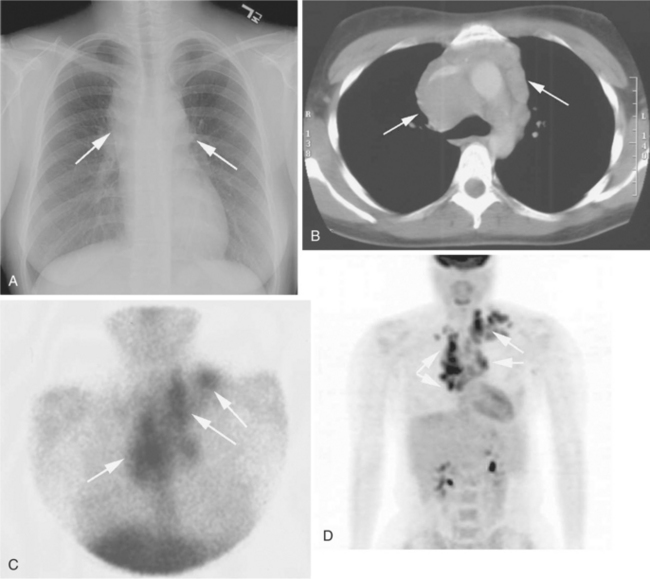

Prognostic indicators for decreased survival in HIV NHL include age greater than 35 years, history of injection drug use, CD4 cell count less than 100/100 ml, a history of AIDS before the diagnosis of lymphoma, stage III or IV disease, and/or elevated LDH levels.110